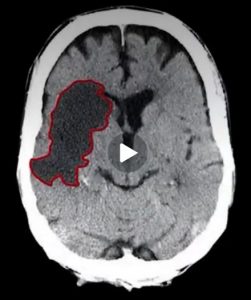

Patient Suffered Large Right Hemispheric Stroke

According to a court document, the cannulation of the carotid artery remained undetected for approximately 7 hours.

“Prolonged arterial cannulation can result in thrombus formation and stroke.”

At 6:05 pm, acting on a comment by a family member, the staff observed that Ms. Shoemaker had difficulty following commands and moving her extremities. A Code Stroke was called at 6:30 pm.

A CT angiogram showed a completely occluded right hemisphere of the brain. Chesta Shoemaker had suffered a large vessel stroke. A neuro exam revealed “brainstem dysfunction with possible progressive cerebral edema that could progress to brain death.” Ms. Shoemaker was transferred to the Neuro ICU. Though a thrombectomy was performed to remove the blood clot, it was too late. Recovery was not possible. Ms. Shoemaker’s family and friends came to be with her on her last day. Chesta Shoemaker’s life support was withdrawn on the evening of April 14, 2017. She passed at 10:26 pm. The Report of Death indicated the stroke resulted from “tearing of the right carotid artery.”